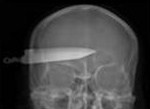

Em indivíduos que se encontram no estado de esqueleto, a causa da morte só pode ser estudada relativamente a situações que deixem marcas nestas estruturas como as fracturas, ferimentos por armas de fogo ou marcas de intoxicações crónicas pelo arsénio, sendo o raio-X uma técnica muito importante.